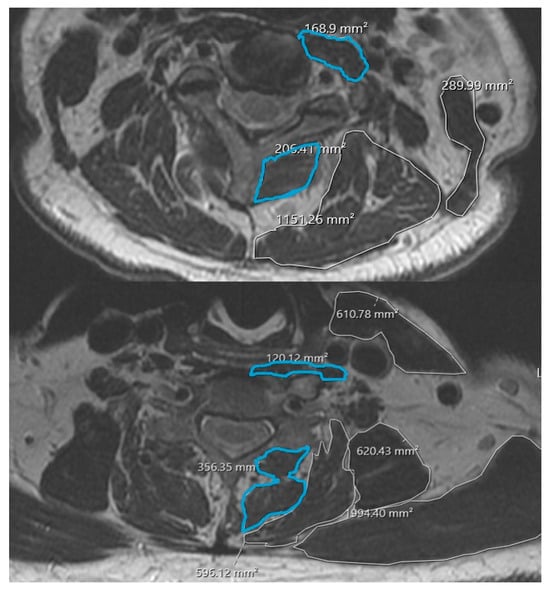

2.3. MRI-Based Cervical Paraspinal Muscle Health Measurements

3.2. Cervical Paraspinal Muscle Cross-Sectional Area